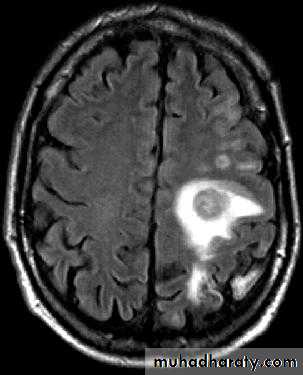

• B. Radiological Investigations:

• CT or MRI is the investigation of choice.

• CT Brain is performed with and without contrast.

• MRI is done with gadolinium enhancement.

• They will show a single (or multiple) space occupying lesion that is well delineated with an enhancing wall, with variable surrounding oedema.

Brain Abscess CT with contrast

Brain Abscess MRI